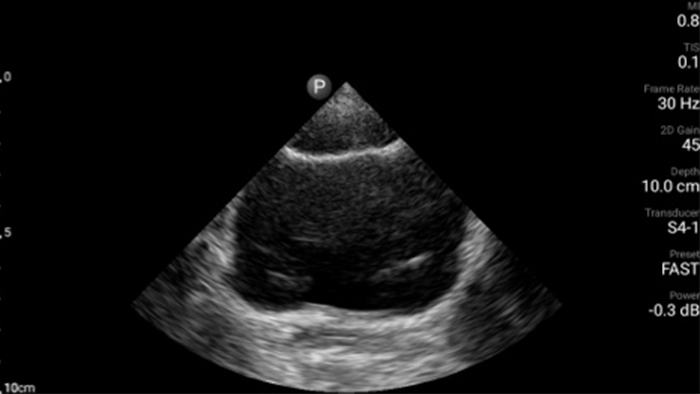

Actúe más rápido para proteger el corazón de sus pacientes

Cuando los segundos cuentan, el ultrasonido portátil puede marcar la diferencia. Lumify puede proporcionar las imágenes de alta definición que requiere cuando y donde las necesite.

Oportunidad de revertir potencialmente la miocardiopatía

Tutorial

Introducción a la ecocardiografía transtorácica